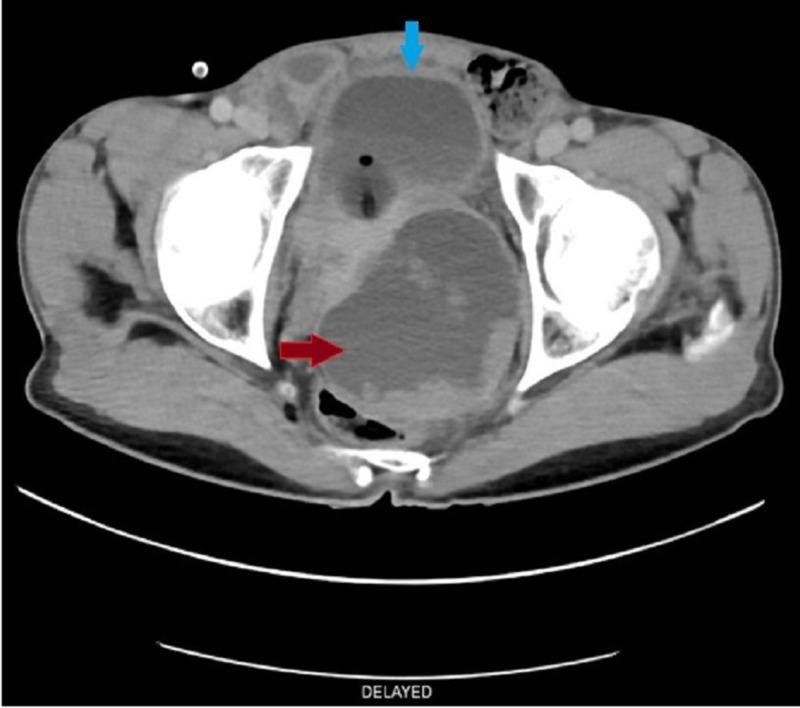

Prostatic ductal adenocarcinoma, is an uncommon entity in the spectrum of prostatic carcinoma. Clinically it is different from common prostatic acinar adenocarcinoma. It is usually more aggressive than prostatic acinar adenocarcinoma. We are presenting a case report on prostatic ductal adenocarcinoma, a cystic variant of prostatic carcinoma in a 55-year-old man who complained of obstructive urinary symptoms with mildly raised prostate-specific antigen (PSA). On further evaluation in our radiology department a cystic lesion with enhancing polypoidal soft tissue component was noted in prostatic parenchyma. Histopathology confirmed the diagnosis of ductal adenocarcinoma.

前列腺导管腺癌是前列腺癌谱系中一种不常见的类型。在临床上,它与常见的前列腺腺泡腺癌不同。它通常比前列腺腺泡腺癌更具侵袭性。我们报告一例前列腺导管腺癌病例,这是一名55岁男性的前列腺癌囊性变异型,他主诉有梗阻性排尿症状,前列腺特异性抗原(PSA)轻度升高。在我们放射科进一步评估时,发现前列腺实质内有一个伴有强化息肉样软组织成分的囊性病变。组织病理学确诊为导管腺癌。